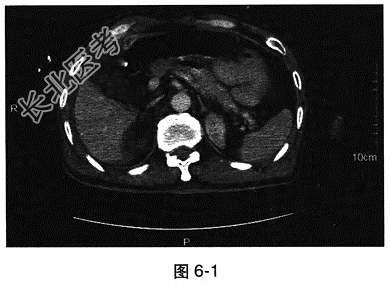

- 多项选择题4.[提示]腹部增强CT检查见图6-1。行腹腔诊断性穿刺,抽出少量浑浊的血性液体。送检腹水常规、生化及细菌涂片。

下一步合理的处置包括 A、收住病房继续观察

B、腹腔灌洗

C、等待腹腔穿刺液化验结果

D、抗生素治疗

E、急诊行剖腹探查术

F、胃肠减压